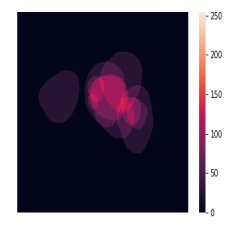

In total, we have generated synthetic polyp images and the corresponding masks. SinGAN-Seg generates random samples with high variations when the input scale is . This variation can be easily recognized using the standard deviation (SD) and the mean mask images presented in Fig 5. The mean and SD images were calculated by stacking the generated mask images corresponding to the synthetic images related to a real image and calculating pixel-wise std and mean. Bright color in std images and dark color in mean images mean low variance of pixels. In contrast, dark color in std and bright color in mean images reflect high variance in pixel values. By investigating Fig 5, we see that small polyp masks have high variance compared to the large polyp mask as presented in the figure.

To understand the difference between the mask distribution of real images and synthetic images, we plotted pixel distribution of masks of synthetic images in Fig 6. This plot is comparable to the pixel distribution presented in Fig 3. The randomness of the generations made differences in the distribution of true pixel percentages compared to the true pixel distribution of real masks of real images. However, the overall shape of synthetic data mask distribution shows a more or less similar distribution pattern to the real true pixel percentage distribution.